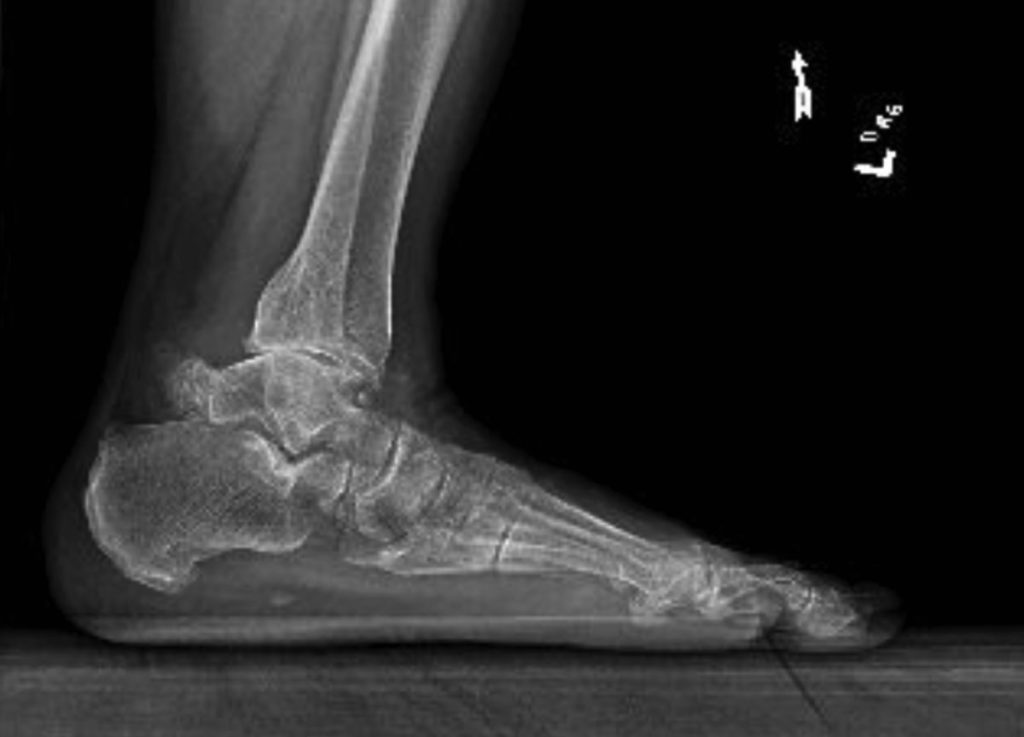

Imaging. Once objective and subjective values have been collected, the clinician should obtain a lateral ankle plain film to confirm or rule out a fractured os trigonum. A positive fracture site is marked by separation and a rough, jagged edge in the region of the os trigonum (Figure, page 54). Smooth areas on the radiograph are a sign that there is no fracture.